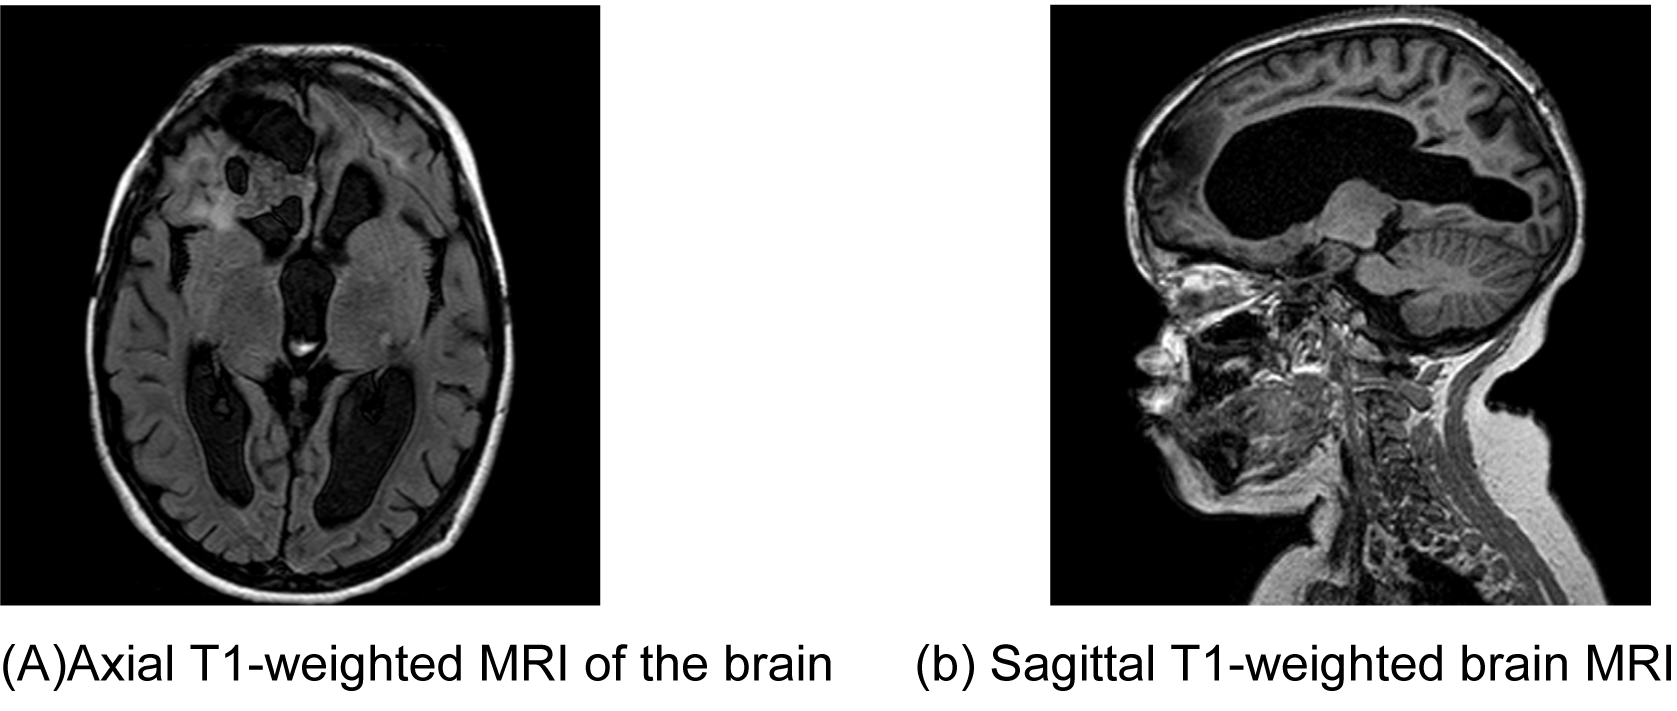

An eight-year-old boy was referred by an ophthalmologist to the Pediatric Oncology Center (Cape Town) in 2004. He presented with features of hypopituitarism and bilateral optic atrophy. His imaging studies showed a ring enhancing lesion with solid and cystic components arising from the suprasellar area and compressing the third ventricle (V3) with associated hydrocephalus. A subtotal resection and left subdural shunt was performed at that time, and a histological diagnosis of CP was made hormonal replacement was initiated. A year later following his first recurrence the patient was treated with repeat debulking resection and at this time an Ommaya reservoir was placed. Further subtotal resection to the growing lesion, followed by adjuvant radiotherapy (54 Gy) was done the following year after he had turned three years old. At this point, multi-modality treatment allowed for disease stability for another three years, when evidence of disease progression was again noted. This prompted surgical re-intervention and a debulking procedure was again performed. In June 2011, at the age of eight, radiological evidence of tumor recurrence was again noted (Figure 1A-B) and after multi-disciplinary discussion, treatment with intracystic IFNa-2b was proposed as an alternative method of gaining local control and thereby controlling disease progression. A pre-treatment leakage test was done via the Ommaya reservoir and this showed extensive leakage around the catheter into the right ventricle. (Figure 2) There was thus concern over the potential for leakage during IFNa-2b treatment and the clinical implications of this were researched. The treating multi-disciplinary team enlisted further advice from international colleagues regarding the safety of IFNa-2b administration in such a situation. Following this advice and the information obtained through documented research, a decision was made to proceed with the therapy as intra-ventricular spillage of IFNa was considered to be innocuous. The first cycle was given intratumorally at a dose of 3,000,000 international units. This dose was then administered three times a week for a total of four weeks. During these treatment sessions, the patient exhibited severe lethargy. Two weeks after completing the full planned course he presented with confusion, urinary incontinence and was found to have hypernatremia and hyperthyroidism. Magnetic resonance imaging (MRI) of the brain, at that point revealed significant brain atrophy, striking volume loss with no significant change in the tumor size and an increase in hydrocephalus. (Figure 3A-B) The patient was admitted and his condition stabilized following appropriate management. His hormonal replacement medications were adjusted and a shunt was inserted to drain the re-accumulating hydrocephalus. He was seen again in the combined Pediatric Neuro-Oncology clinic a month later, and was clinically stable. It was thus decided to forgo further IFNa-2b therapy due to concern about further complications. He will thus be followed at regular intervals for symptom control and monitoring of his endocrine functions. | ||||||